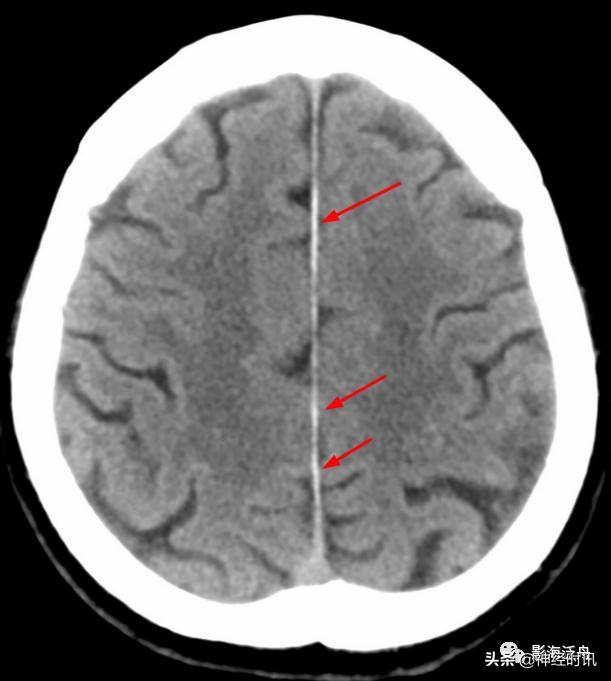

典型的大脑镰前部少量蛛血,血肿的边缘毛糙(红箭)且抵达胼胝体膝部的前缘(黄箭头)。4天后复查头颅CT平扫,相应部位少量蛛血基本吸收。

另一例表现类似的大脑镰前部少量蛛血,血肿的边缘总是有一种毛毛糙糙的感觉(红箭)。